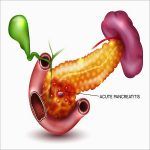

Viêm Tụy I Bài giảng CĐHA *

Viêm tụy cấp (Acute Pancreatitis) là một quá trình viêm cấp tính của tụy, biểu hiện ở nhiều mức độ khác nhau: mức độ nhẹ chỉ cần nằm viện ngắn ngày, ít biến chứng. Mức độ nặng, bệnh diễn biến phức tạp, tỷ lệ tử vong cao 20-50%, trong bệnh cảnh suy đa tạng, nhiễm trùng…